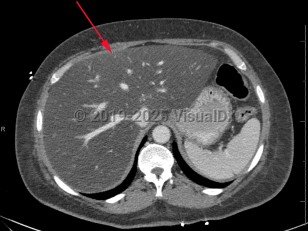

Metabolic dysfunction-associated steatotic liver disease

Screening for MASLD is of the utmost importance in patients with underlying risk factors, primarily obesity and metabolic syndrome, as it is often asymptomatic. Some patients report vague symptoms such as fatigue or mild right upper quadrant abdominal pain. If MASLD progresses to cirrhosis, patients will often present with signs and symptoms of advanced liver disease: spider angiomata, gynecomastia, ascites, jaundice, and peripheral edema.

The primary risk factors for MASLD are central obesity, type 2 diabetes mellitus, and hyperlipidemia. Modification of these risk factors, mostly through weight loss and dietary and lifestyle changes, is the most effective preventive and treatment strategy.